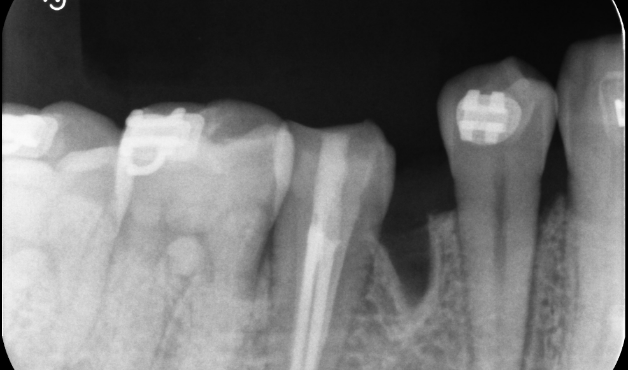

Under Treatment

主訴

インプラントはできないが、入れ歯もしたくない

治療内容

自家歯牙移植 / イニシャルトリートメント(大臼歯)レジンコア

治療期間

3ヶ月

治療費用

550,000

治療の

リスク

術後しばらくしてから骨性癒着、外部吸収を起こす可能性があります。